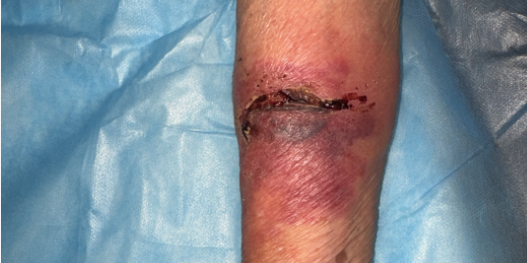

首次上门评估时,付红菊发现李爷爷的创口问题比预想中更复杂严重:创口面积几乎横跨整个小臂内缘约7*4cm大小,周围皮肤组织红肿范围约3—4cm,伴皮下出血性红斑,不仅有局部炎症反应,还存在皮下出血,创面甚至有黄色分泌物并伴随轻微渗血。

“必须立即清创消毒控制局部感染,不然感染加重,伤口更难愈合!”结合李爷爷的基础病史,付红菊迅速调整处理方案,为他制定了个性化的上门护理计划。